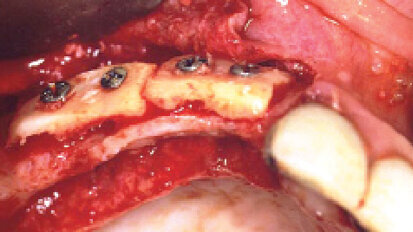

Horizontální augmentace kosti

Dr. Riz Syed hovoří o významu augmentace kosti na poli implantologie a některých možnostech léčby. Dentální ...